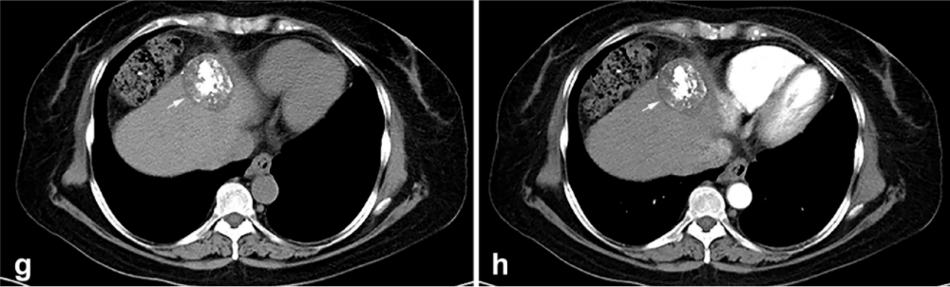

背景:由于一些原因,位于膈肌附近的肿瘤的热消融在技术上具有挑战性。首先,术中计算机扫描和超声检查无法清晰显示射频消融/微波消融切缘。第二,消融过程中不利的针分布和过热可能导致肝包膜破裂,并对膈、肺和心脏造成严重损伤。第三,即使使用人工腹水,仍有9~22%的患者因肝周粘连或肿瘤位置靠近肝表面而导致膈肌热损伤。冷冻消融可能是毗邻膈肌的HCC的一种有前途的治疗方法,因为在消融过程中使用CT和US可以很好地显示肿瘤边缘。尽管一些研究评估了在高危区域使用冷冻消融治疗HCC,但很少有研究针对膈肌临近区域。

背景:肝癌是中国最常见的恶性肿瘤之一,发病率和死亡率都很高。虽然手术切除是最好的治疗方法,但大多数患者处于晚期或直到住院才有手术指征。对于单个肿瘤直径小于5厘米的患者,微创治疗与手术切除效果相当;多个病灶小于3个,单个病灶最大直径小于3cm;不侵犯血管、胆管、邻近器官和远处转移。虽然一些传统消融技术方式可以使部分患者受益,但不适用于特殊部位肝癌(定义为毗邻大血管、肝外脏器和重要结构的肿瘤)的治疗。冷冻消融作为一种相对较新的治疗方式,具有明显的冰球效果、疗效好、激活抗肿瘤免疫、并发症发生率低等优点,尤其适用于特殊部位肝癌患者的治疗。我们的研究目的是探讨CA治疗特殊部位肝癌的安全性、可行性和有效性。

① 在我们的研究中,技术成功率为100%。动态增强MR检查随访1个月,66例患者首次技术有效率为65例(98.5%),MR影像学未发现外周脏器损伤。中位随访时间14个月(范围2-28个月)。高危部位肝癌局部肿瘤进展率曲线:6、9、15和24个月的累积局部肿瘤进展率分别为10.2%、16.5%、20.9%和30.5%。